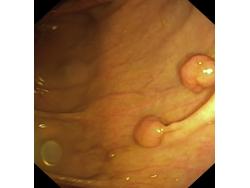

Polipy